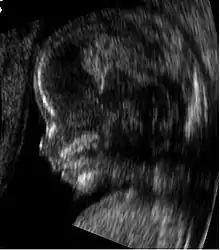

| 12 weeks | Uterus is the size of a grapefruit | Head grows faster than the rest of the body; facial features are apparent, but there is no layer of fat yet and the skin is translucent; gender can be distinguished via ultrasound; fingernails appear |

- By 20 weeks the fetus will be about 6 1/3" long and weighs 12 oz. Movements are for more coordinated. The sexual organs are well developed and are usually visible on ultra sound.